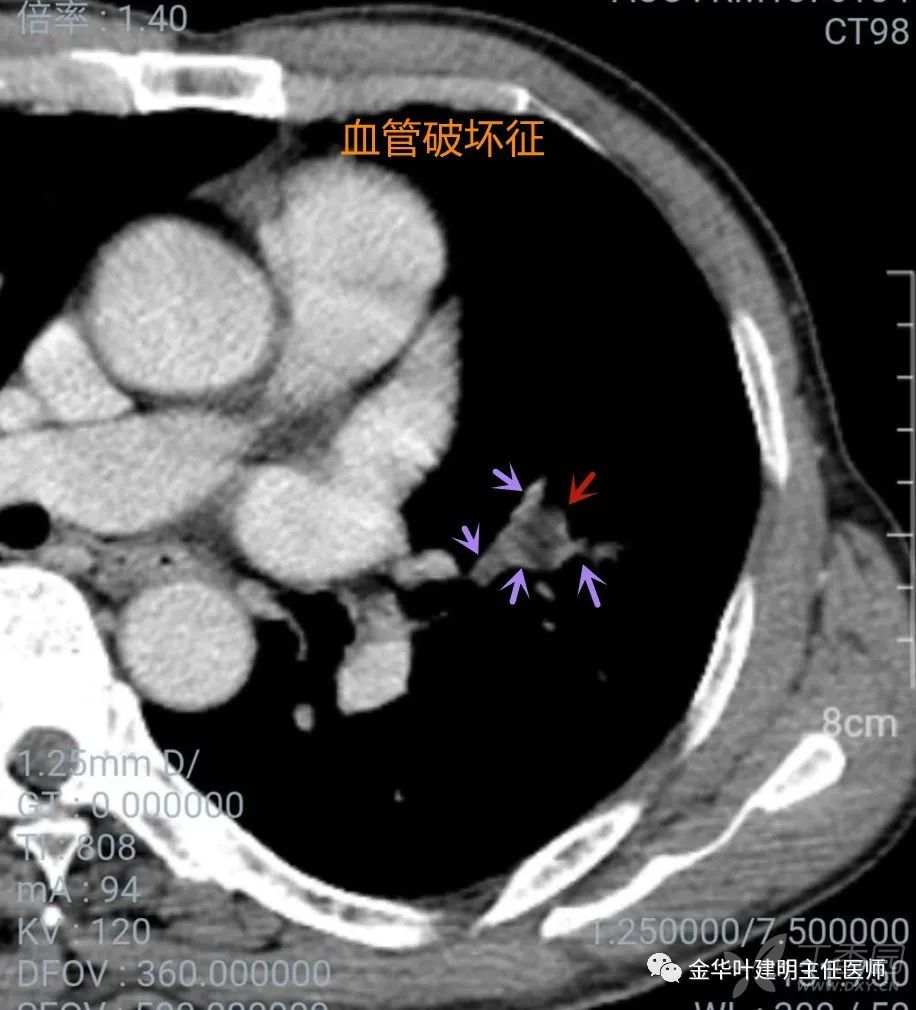

血管破坏征

血管破坏征:有时候,病灶比较小,又不适合穿刺的地方,实性,良恶性特征了不太显著,需要我们增强或重建以观察血管与病灶的关系,如果紧挨病灶的血管走行异常,被牵拉向病灶侧、被侵犯,或者血管与病灶间间隙消失,则要怀疑恶性,有血管破坏。